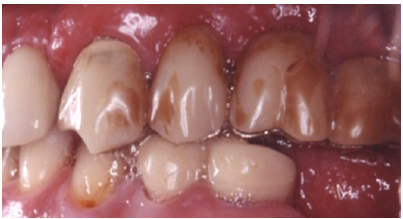

Figure 4: Preoperative intraoral left side view.

The patient reported a free medical history, but admitted smoking habit (20+cig/day). He was not taking any medication and reported pain in facial muscles during stressful periods. The patient was subjected to thorough clinical and radiographic examination (panoramic x-ray) (Figure 2). Intraorally, he presented severe abrasion most observed in mandibulary dentition, reduced VDO, and several missing mandibular teeth (#44,45,46,47 and 36,37). In the maxilla, a 4-unit metal ceramic bridge with a cantilever was found on the incisors {12-11-21-(22)}, and one 4-unit metal-acrylic bridge in the posterior segment {23-(24)-(26)-27}. The visible diastemmas between #12,#13 and #13,#14 were due to a missing premolar #15 which probably caused distal migration of #14 and 13 (Figure 3-5). The smile line was evaluated as medium (Figure 6). Secondary caries was visible in amalgam restorations in #14 and #16 and was inspected under the abutment #12. A significant change in the occlusal plane was obvious, defined by significant protrusion of #13, #14 and #16. In the mandible acrylic crowns were positioned in #44, 33, 34. Initial radiographic examination revealed endodontic therapies in #12, 34, 35, 42 and #43 and it was estimated that the bone level averaged at 70%. Clinical examination of the stomatognathic system revealed bilateral myalgia of the lateral pterygoid muscles on palpation, unilateral clicking on the left TMJ and limitation in mouth opening. All other masseter muscles were free of symptoms.